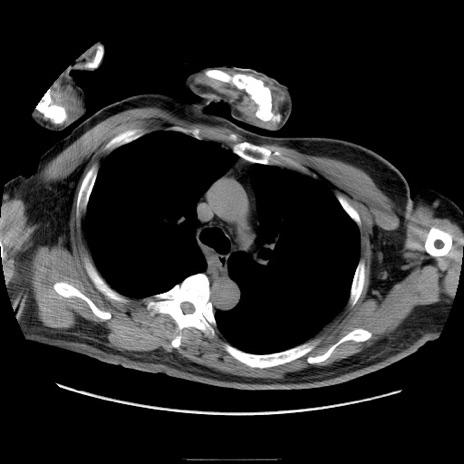

症例22(横断像)

【症例】50歳代男性

【主訴】腹痛

【現病歴】AVMからの被殻出血のため回復期リハ病棟入院中。 本日午後3時頃急に下腹部痛が出現した。

【既往歴】AVM、被殻出血、虫垂炎、高血圧

【身体所見】意識晴明、左半身不全麻痺、会話の理解は良好、36.5°C、腹部:膨隆、全体に板状硬、下腹部正中に圧痛点あり、反跳痛-、筋性防御不明、右下腹部にope scar

【データ】WBC 9400、CRP 0.06